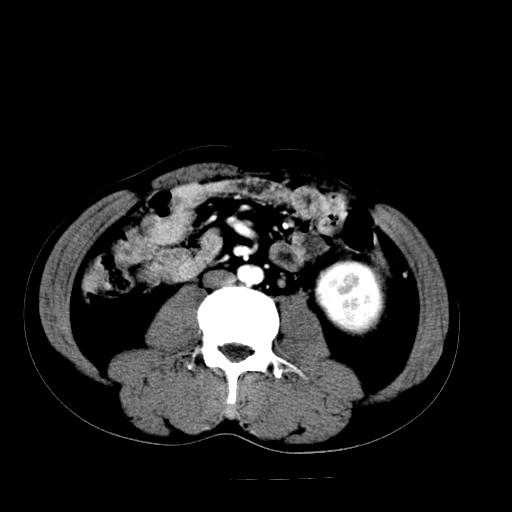

以下是引用天南地北在2007-4-30 13:36:00的发言:[br]支持慢性胰腺炎伴有假性囊肿

以下是引用andymaomao在2007-4-30 14:28:00的发言:[br]支持:1.慢性胰腺炎并假性囊肿形成可能;[br] 2.左肾形态稍增大,旋转不良。